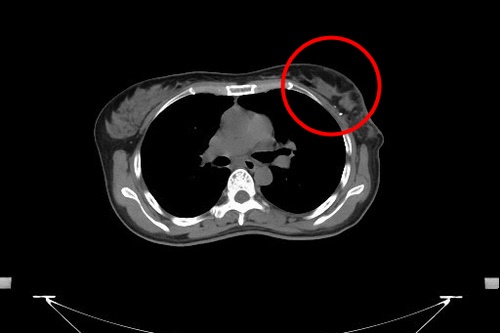

乳房醫學中心張群明主任表示,若是腫瘤較大、多發性腫瘤、腫瘤位於乳房中央或侵犯乳頭、乳房攝影顯示廣泛性或多發性癌樣鈣化點(原位癌)、發炎性乳癌、手術後不做放射線治療,以上任一種情況都建議做乳房全切除手術;但若腫瘤較小,切除後乳房仍能保有良好外觀且能接受手術後放射治療的病友,則適合乳房部分切除手術(保留手術)。

早期乳癌患者有些人的腫瘤較小,不需將整個乳房切除,除了可以做部分乳房切除手術,並可同時進行整型式乳房重建手術。切除腫瘤保留部分健康的乳房組織,並將組織轉位來填補切除腫瘤後所留下來的乳房空洞,重建乳房的缺損,手術後乳房的外觀不會產生明顯的凹陷,能保留較佳的外觀,整型式乳癌切除手術也是目前乳房手術的趨勢。